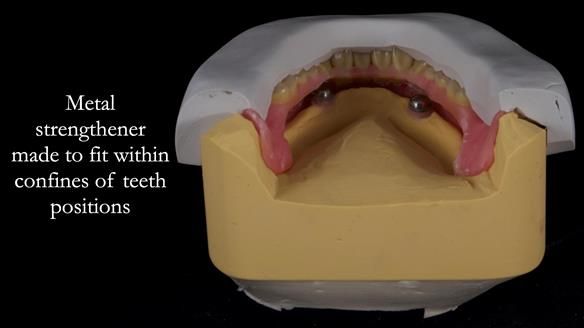

1. The four implants appear clinically and radiographically healthy, though their longevity is uncertain.

2. The upper denture, horseshoe-shaped and metal-reinforced, rocks on the ridge, causing wear on Locator abutments and a fractured upper right tooth.

The detailed clinical situation and treatment process are outlined below, with clinical work provided by me and technical work by Rowan Garstang. New complete implant supported complete dentures were made. The new upper denture had ‘almost’ full palatal extension for the non-splinted implants following ITI guidelines. A decision was reached to retain the worn Kerator attachments, as their removal could potentially accelerate implant failure. The treatment spanned five visits for denture fitting and one review. Alisdair expressed great satisfaction with the treatment, noting a significant enhancement in his overall quality of life.